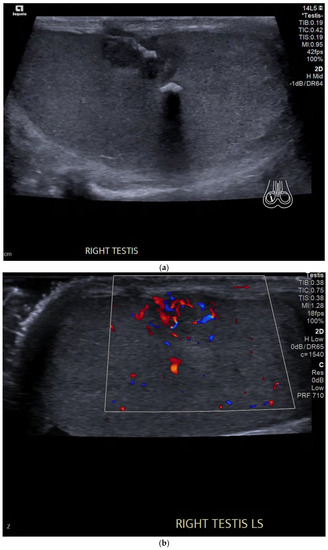

4.3. Embryonal Cell Carcinoma

| Pure embryonal | Heterogeneously hypoechoic Ill-defined margins with invasion of the tunica albuginea Can contain haemorrhage and calcifications |